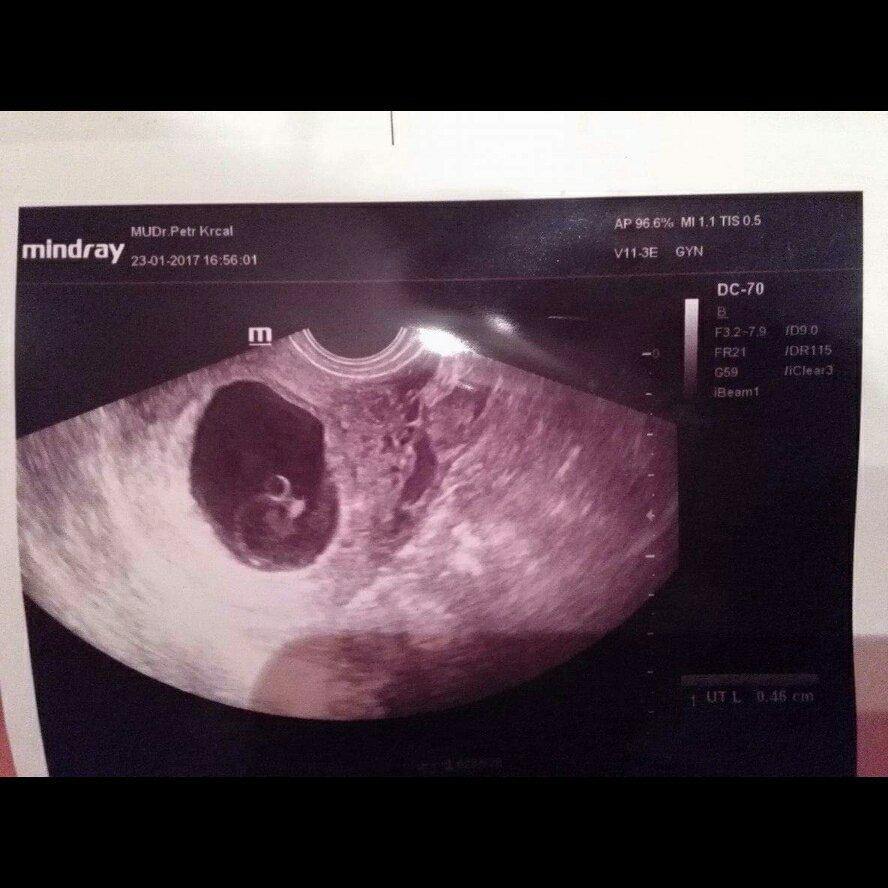

@trrr, @tornadolu, @arielka222, @ple, @luska@lucinka58, @janinasvecova, @digisek, @simi1510, @leymea, @kstablova, @snezenka123,@jarmulka tak jsem konečně doma. Tak ještě dnes nepadl naštěstí poslední verdikt. Mimisek povyrost o 9 mm, srdečný akce ještě není, ale prý ještě počkáme do pátku, tak snad srdíčko se rozběhne. Přítel se na všechno poptal, takže ted alespoň tak nějak víme, co se děje. Tak ta velká bublina je prý ten gestační váček, ve kterým by embryjko mělo být, ale je mimo ní. tzn.že do pátku by se mělo dostat do té bubliny dovnitř. Jinak co se týče tech rozměrů, tak vše prý je v mm, ne v cm, jak jsme si mysleli 🙂 0,46 cm. Takže ted už nezbývá než doufat, ze v pátek se ukáže srdíčko. Přikládám UTZ 🙂